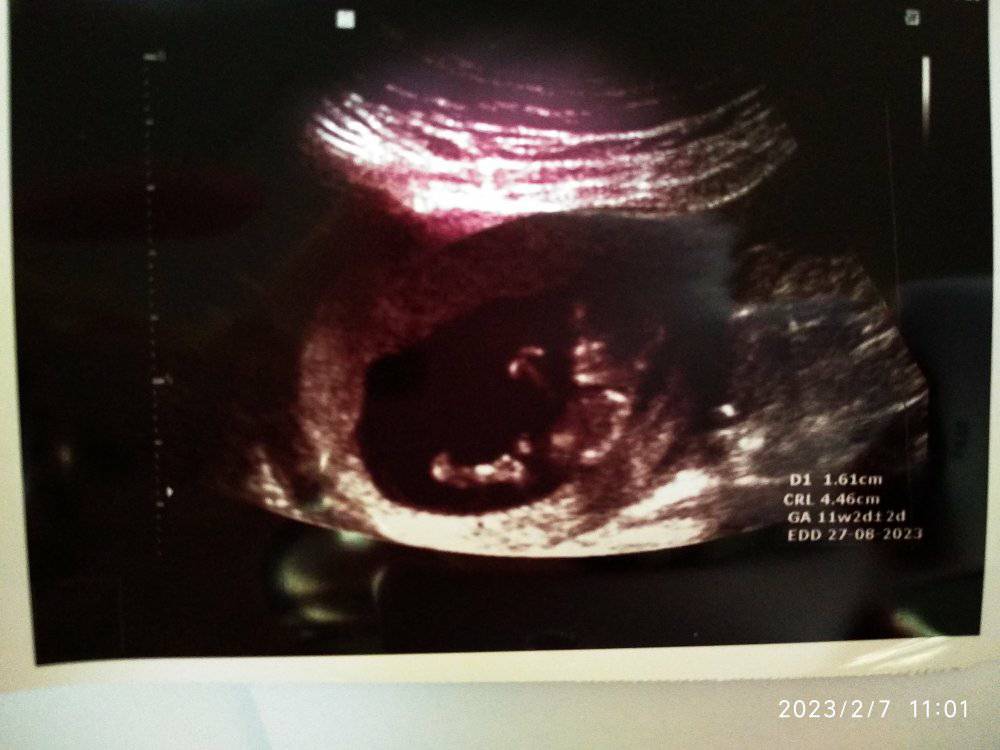

Nub theory guesses

Attachment 43755

I just had my ultrasound at 10w6d, and I am hoping some of you would like to guess if it's a girl or a boy. I am not sure if it's too soon for the nub theory but it's worth taking a shot until I get my NIPT test results, then I will know for sure. :baby2: